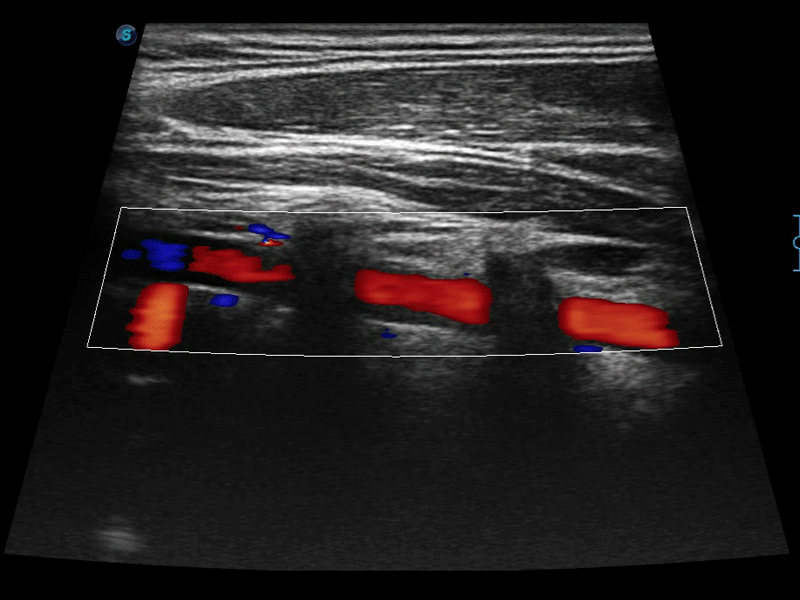

通过色彩血流和实时宽景相结合,可观察到完整的静脉或动脉的血流,方便医生检查。实时扫查过程中,如有任何操作失误也可以很容易地进行回扫擦除,而不会中断扫查。